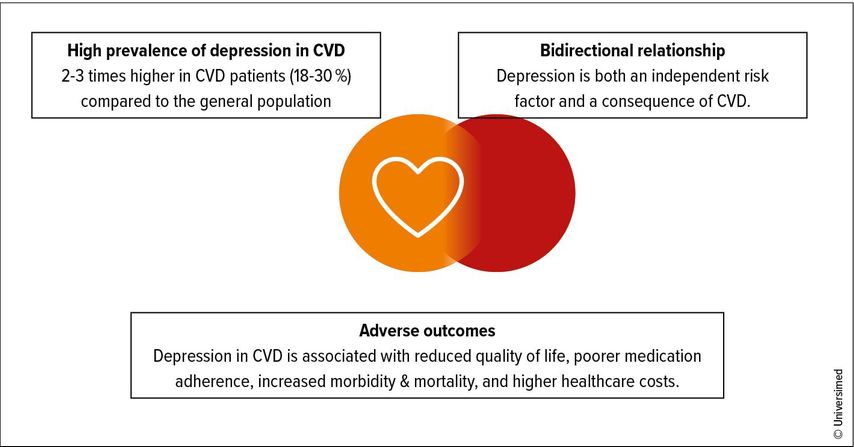

Cardiovascular disease (CVD) remains the leading cause of morbidity and mortality worldwide.1 While advances in disease-specific management have substantially reduced mortality, longer life expectancy has also brought an increase in comorbidities. Among these, depression remains an important yet underrecognized condition. Mental health conditions, including depression, are among the leading causes of disability worldwide.2 In patients with CVD, its prevalence is two to three times higher than in the general population. Between 18% and 30% of patients with coronary artery disease live with depression, with even higher rates in heart failure (up to 40%) and post-stroke populations (up to 50% at five years).3–5 Women are disproportionately affected, with nearly double the prevalence compared to men. Beyond prevalence, depression independently predicts worse cardiovascular outcomes, resulting in increased hospitalizations, higher healthcare utilization, reduced quality of life, poorer treatment adherence, and higher mortality.6 Recent Mendelian randomization studies even suggest a causal relationship between depression and cardiovascular events, particularly coronary artery disease, myocardial infarction, and small-vessel stroke.7,8

Clinical practice guidelines are designed to translate evidence into standardized, actionable recommendations. In areas such as diabetes, hypertension, and dyslipidaemia, guideline-directed care has transformed outcomes. Yet, the picture is markedly different when it comes to depression in CVD (Fig.1).6 Our review of 65 CVD guidelines across five continents revealed a gap between recognition of depression as a risk factor (71%) and provision of guidance: Only 23% included both screening and treatment recommendations (37% screening; 34% treatment), fewer than 3% addressed drug–disease interactions, an important concern given the high prevalence of polypharmacy in this population. Notably, just 12% involved mental health specialists in their development.6 Entire CVD areas, such as peripheral artery disease (PAD) and aortic disease, were almost silent on the issue of depression (Fig.2).6 Where recommendations existed, they varied widely in scope, specificity, and evidentiary strength. Screening was often encouraged, typically using PHQ-2 or PHQ-9, but without practical advice on implementation.6 Treatment recommendations ranged from psychotherapy and physical activity to SSRI, yet supporting evidence was often graded as low to moderate.6 Few guidelines addressed drug–disease interactions, despite polypharmacy being common in this population.6 This lack of systematic, high-quality guidance perpetuates underdiagnosis and undertreatment, leaving clinicians uncertain and patients at risk (Fig.3).

Fig. 1: Depression & cardiovascular disease: a critical clinical challenge (see Armon DB et al. 2025)6